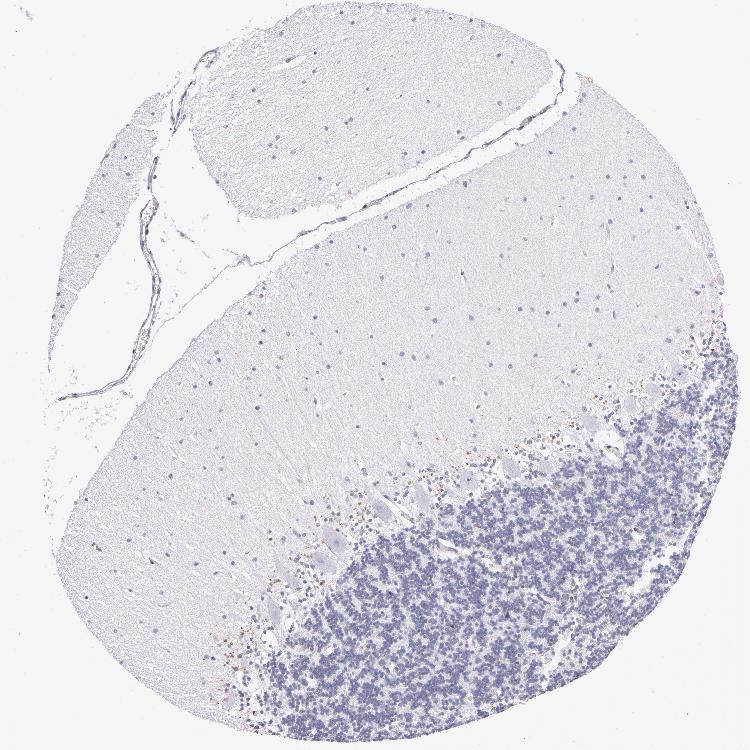

BRAIN CEREBELLUM Show tissue menu

CEREBELLUM - Expression summary

Protein expression

Cerebellumi

On the top, protein expression in current human tissue, based on all annotated cell types, is reported with the units not detected (n), low (l), medium (m) and high (h). Underneath, protein expression in each annotated cell type are reported using the same units.

Protein expression data is based on knowledge-based annotation. For genes where more than one antibody has been used, a collective score is set.

If knowledge-based annotation could not be performed for a gene, no data is displayed here. View antibody staining data further down this page.

h

m

l

n

Cells in granular layer: Not detected

Cells in molecular layer: Not detected

Purkinje cells: Not detected

CEREBELLUM - Antibody stainingi

Antibody staining in the annotated cell types in the current human tissue is reported as not detected, low, medium, or high, based on conventional immunohistochemistry profiling in selected tissues. This score is based on the combination of the staining intensity and fraction of stained cells.

Each image is clickable and will lead to virtual microscopy that enables deeper exploration of all samples and also displays staining intensity scores, fraction scores and subcellular localization as well as patient and tissue information for each sample.

Antibody HPA069497Antibody CAB002786Antibody CAB069881

Purkinje cells Not detectedNot detectedNot detected

Cells in granular layer Not detectedLowNot detected

Cells in molecular layer Not detectedNot detectedNot detected